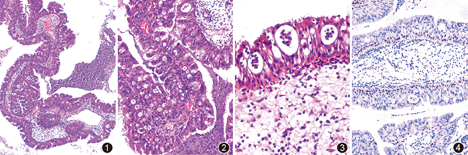

病理检查:大体检查:送检标本均为灰白、灰红色破碎组织,例1约4.5 cm×3.5 cm×2.0 cm大小,例2约3.0 cm×2.5 cm×2.0 cm大小,无包膜,表面较光滑,部分可见乳头状、息肉状结构,质软,可见出血、水肿、黏液样变半透明区域。镜下观察:例1、2形态学改变相似,低倍镜见肿瘤由粗细不等的乳头状结构构成,乳头状结构同时具有外生性和内生性的生长模式,表面被覆2~8层柱状上皮细胞,上皮层内见丰富的微囊状结构,部分融合呈筛孔样,乳头结构的纤维结缔组织轴心宽窄不一,呈疏松水肿改变,其内大量淋巴细胞、浆细胞、中性粒细胞浸润。乳头之间含有大量炎性细胞、退变细胞的浆液、黏液性分泌物(图1,图2)。高倍镜下肿瘤细胞呈高柱状,长轴垂直于纤维结缔组织轴心,胞质丰富,内含大量嗜酸性颗粒样物,细胞核呈圆形或卵圆形,体积较小,大小形态一致,深染,未见核分裂象。肿瘤细胞亦排列成腺管状或微囊状结构,其内充满黏液样物,部分微囊内含有退变的细胞碎片及数量不等的中性粒细胞,形成微脓肿(图3)。免疫组织化学示:2例肿瘤细胞均表达AE1/AE3、CK7、p53(5%~15%)、CD44;不表达突触素、嗜铬粒素A(CgA)、p16;基底细胞表达CK5/6、p63(图4);Ki-67阳性指数为2%~5%。特殊染色:肿瘤内微囊中的黏液呈阿辛蓝(AB)/过碘酸雪夫(PAS)染色阳性,PAS染色阴性。

病理诊断:鼻腔、鼻窦嗜酸性细胞乳头状瘤。

大体观察OSP大都是暗红色至棕色的乳头状或息肉状病变,组织学上有如下几个特点:(1)同时具有外生性和内生性生长模式、粗细不等的乳头状结构;(2)乳头状结构被覆2~8层高柱状上皮细胞,胞质丰富,内含大量嗜酸性颗粒样物;(3)细胞核呈圆形或卵圆形,大小形态一致,深染,核分裂象少见;(4)黏膜内见数量不等的微囊状结构,其内充满黏液样物,部分可形成微脓肿,黏膜下无黏液囊肿;(5)间质成分从黏液样到纤维化不等,伴有不同数量的炎性细胞和血管成分,固有腺体减少或缺如;(6)乳头状结构之间为浆液性及黏液性分泌物,内含退变的肿瘤细胞碎片、不同种类和数量的炎性细胞。当肿瘤细胞或组织构象出现不同程度的异型性,核分裂计数增高的时候,要警惕肿瘤演变的可能性。OSP的恶变率为4%~17%[1],癌变多数为鳞癌,分化程度高低不等,其次为黏液表皮样癌,在少数情况下,也可以发生其他类型的癌,包括疣状癌、移行细胞癌、小细胞癌、腺癌和鼻窦未分化癌等。癌与瘤可同时存在,也可异时发生,癌灶可为局限性,亦可为广泛性,部分病例内可以查见瘤、上皮异型性增生、原位癌、浸润癌的演变。临床病史与影像学资料对于OSP恶变有一定的提示作用,而全面细致的取材与镜检是尤为重要的。目前OSP在免疫表型方面并无特异性的标志物,肿瘤细胞表达广谱CK、CK7,不表达突触素、CgA等神经内分泌标志物以及p16,基底细胞表达CK5/6、p63等,基底细胞的存在是OSP与浸润性癌鉴别的手段之一,Ki-67阳性指数一般不高,常在5%以下,如高于10%要警惕恶变的可能。肿瘤内微囊中的黏液呈AB/PAS染色阳性,PAS染色阴性。Ingle等[4]报道,CD44染色可以帮助确定肿瘤的性质,其在内翻性乳头状瘤中弥漫表达,而在癌中表达减少或缺如,本组2例OSP病例均标记CD44抗体,均呈弥漫阳性表达,因无癌变区域,无法对照观察OSP癌变区域是否也存在有CD44表达的减少或缺如,希望通过本文能够引起关注,有OSP癌变病例的同仁继续深入探讨。